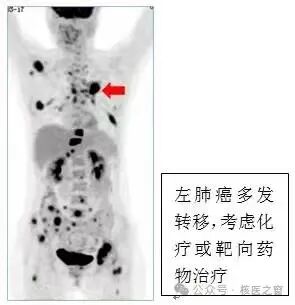

2、明确肿瘤侵犯程度,协助医生为您选择合适的治疗方案

图片